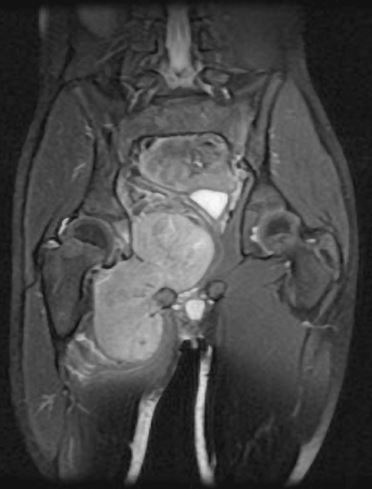

You will be monitored periodically with X-Ray and MRI imaging over the course of 5 years to ensure there are no signs of recurrence. You will have follow up appointments every 4 months for the first 2 years, then every 6 months for the next 2 years, and then once a year. Since the integrity of the limb has been restored to full or almost full, recovery is anticipated provided the patient adheres to strict physical therapy.